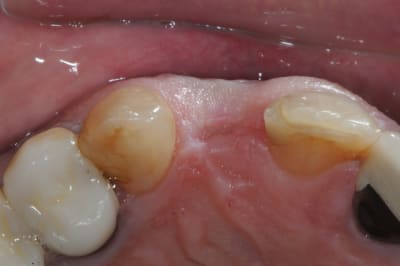

Le cas EII sur 12

positionnement de l'implant en ménageant un espace en vestibulaire qui st comblé avec de l'os synthétique car l'espace est important et il y a une perforation de la corticale vestibulaire en regard de l'apex de la dent.

pour recouvrir tout cela et gagner un peu de volume vestibulaire

un lambeau palatin pédiculé qui après une rotation va recouvrir l'implant et la greffe.